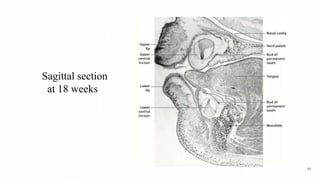

Sagittal section

at 18 weeks